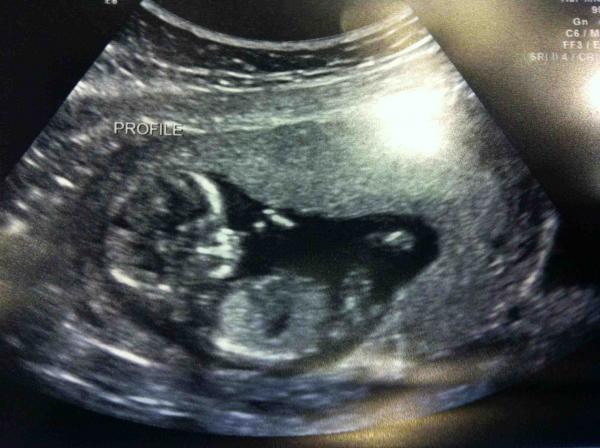

Hi all! I am wondering if I can take advantage of some of your excellent experience. Had an NT scan at 13w6d which I thought would allow for very precise gender prediction (I've heard it's very accurate after 13 weeks) but our tech offered no gender clues whatsoever, and our pics left me without any clear idea of what kind of bundle might be on the way! Can anyone see any gender clues in these pics (I have more, but on my husband's computer which he has at work!) No videos unfortunately :-( .... or will I just have to be patient?

Let me know what you think- thanks in advance!